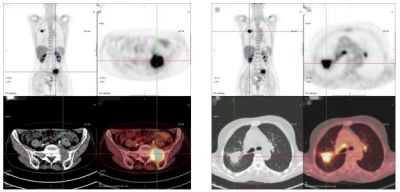

66歲,女,左側腰骶部疼痛1月,ECT檢查示:胸7、骶1及左側髂骨多發骨代謝異常,考慮腫瘤性病變,轉移瘤?

PET/CT診斷:右肺上葉后段結節,代謝增高,考慮原發惡性病變(右肺上葉后段周圍型肺Ca)伴、肺內、淋巴結及多發骨轉移。